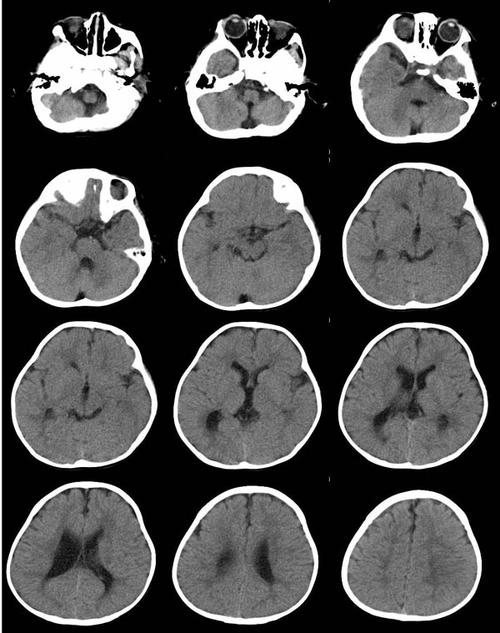

脑白质软化,脑白质脱髓鞘

脑白质病变的影像学鉴别诊断

zt0163:早产儿脑室周围白质软化(pvl)